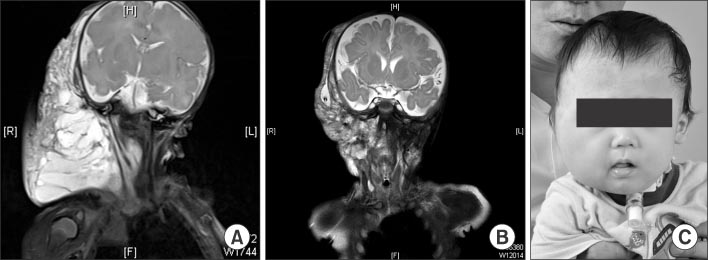

Fig. 5

(A) Sagittal T2-weighted MRI shows cervical lymphangioma which are infiltrating tongue base (patient No. 11). (B) Decreased lymphatic malformation after surgery.